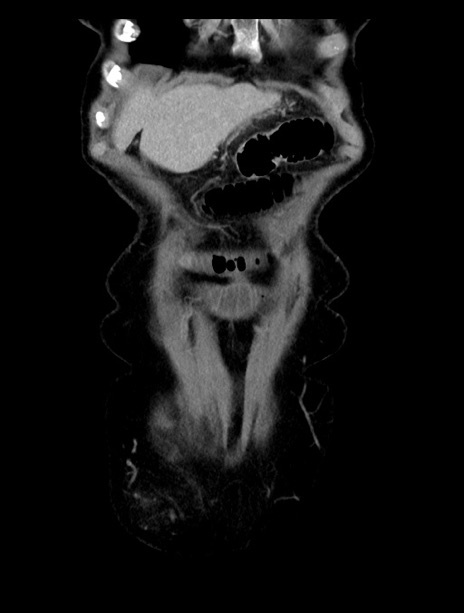

症例23(冠状断像)

【症例】70歳代女性

【主訴】下腹部痛・嘔吐

【現病歴】2日前より腹痛あり。昨日嘔吐あり。症状改善しないため来院。

【既往歴】胃GISTに対して胃部分切除後。

【身体所見】BT 37.1℃、BP 128/77mmHg、腹部:平坦・軟、下腹部に圧痛あり。

【データ】WBC 10200、CRP 0.31